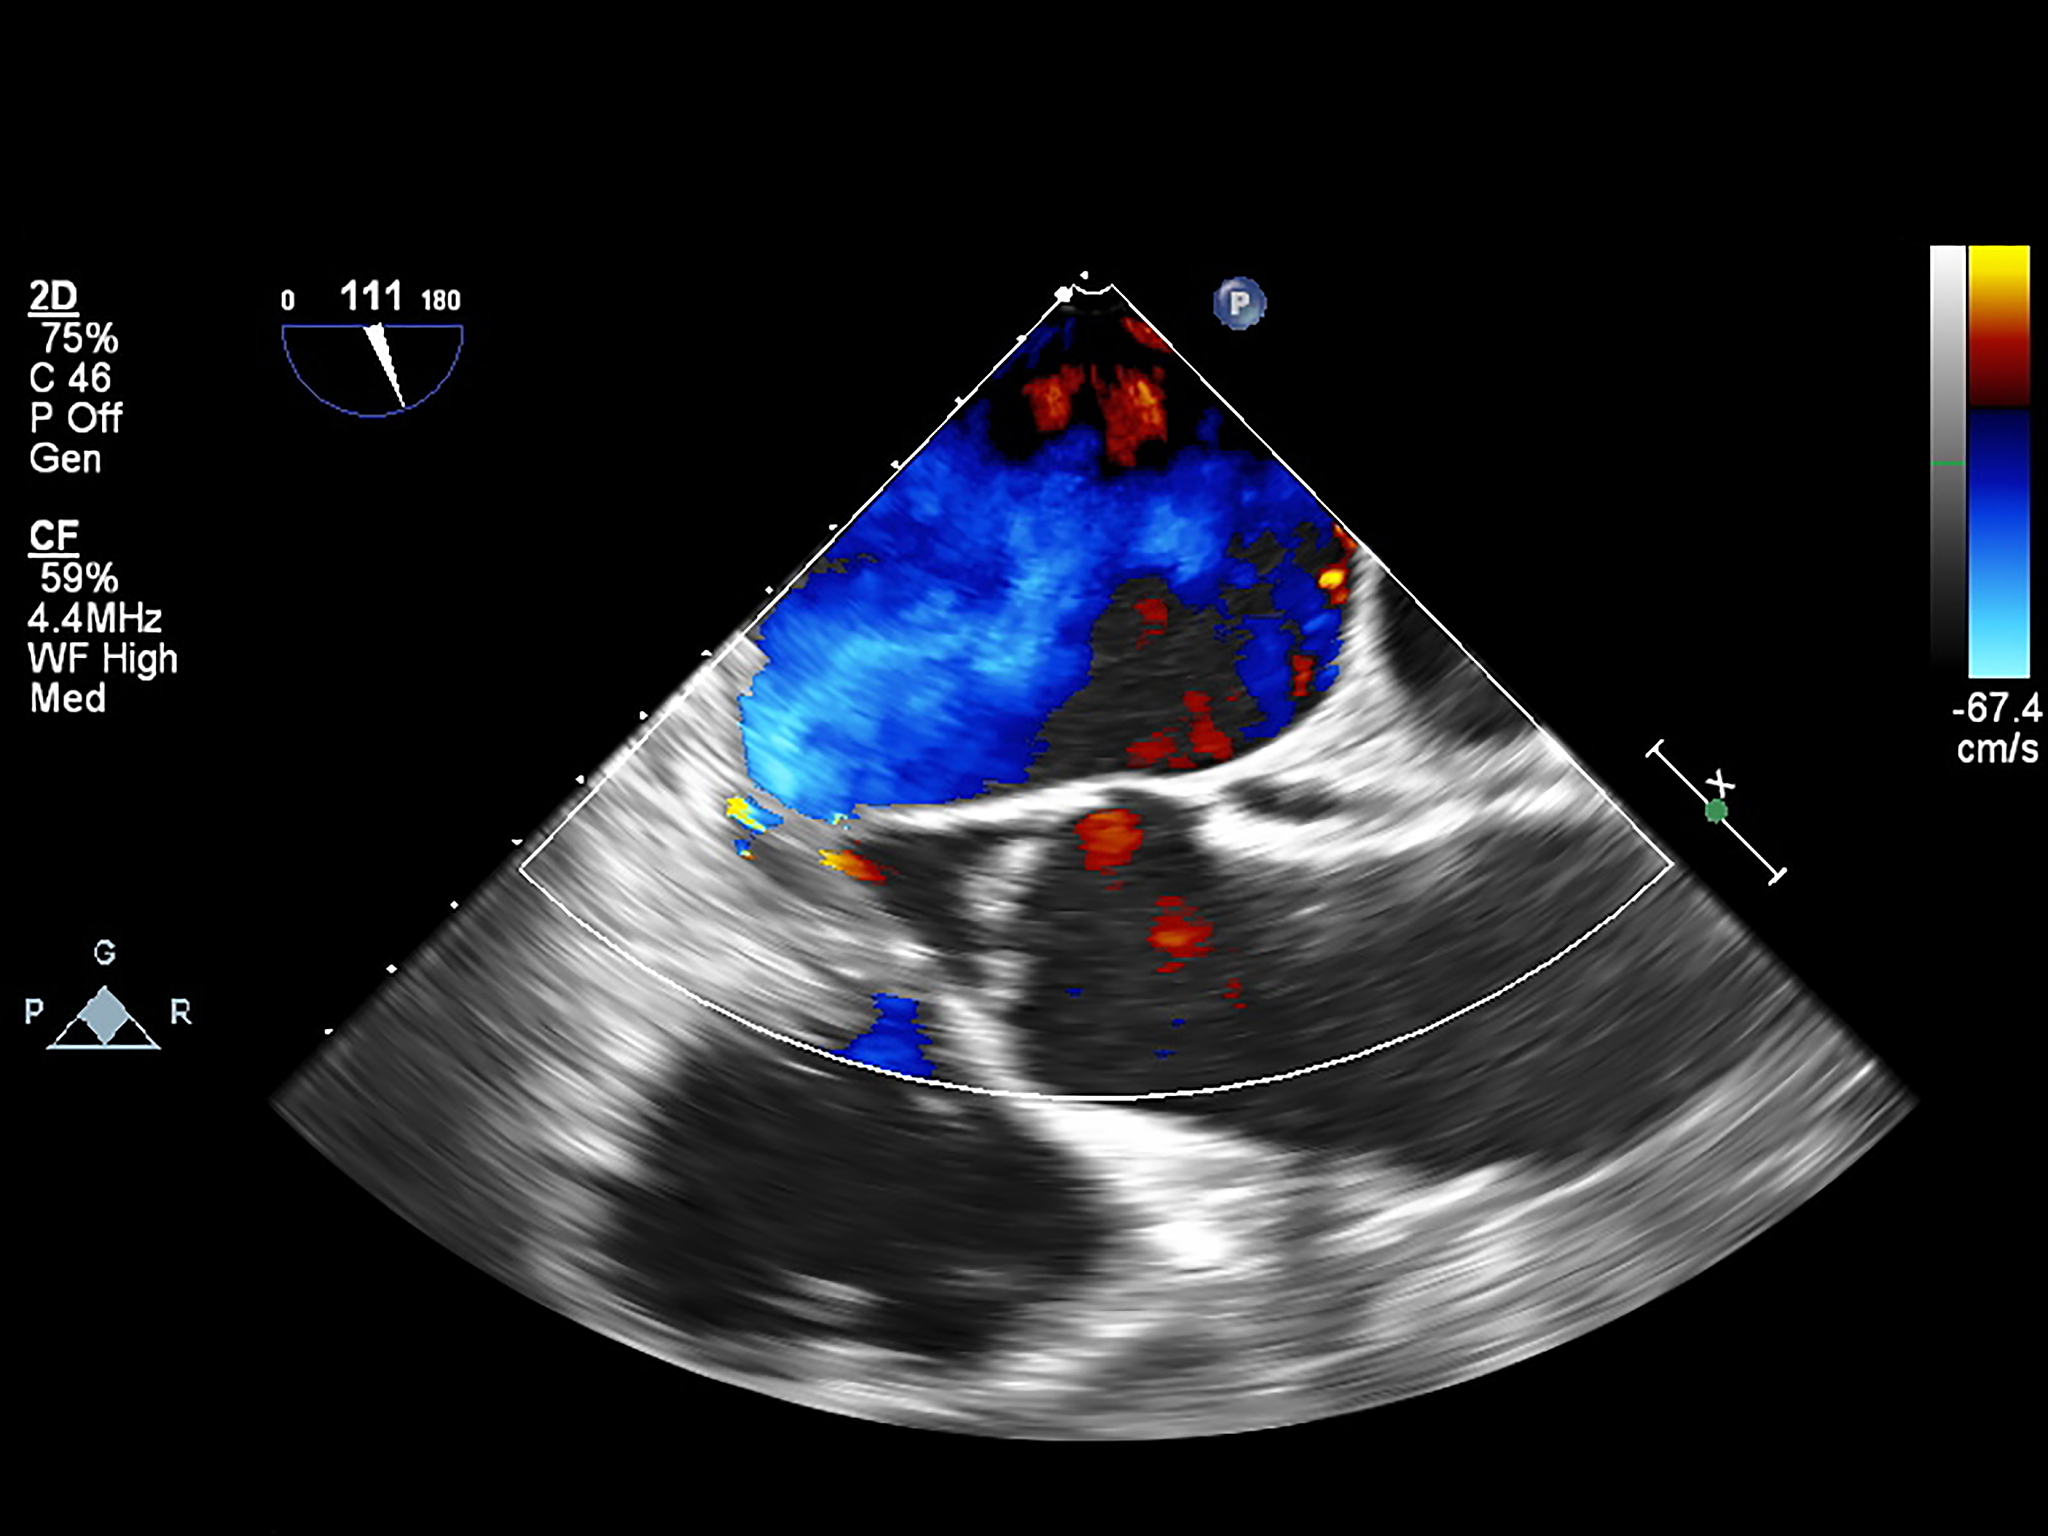

血管内超声诊断导管头端的显影性是指导管头部分在超声图像中的清晰程度和亮度。它的意义在于:

1. 确定导管头位置:导管头清晰亮度越高,表示导管头部分越容易被识别和确定位置,有助于医生准确放置导管。

2. 发现导管头异常:如果导管头部分呈现不规则形状或显影性差,可能是导管头部分发生了异常,需要进一步观察和处理。

3. 判断导管位置和通畅性:导管头显影性好,可以观察导管是否位于正确位置,并且是否通畅,有助于及时发现导管位置异常或者阻塞。

综上所述,血管内超声诊断导管头端的显影性对于导管的放置、观察和处理都具有重要意义。